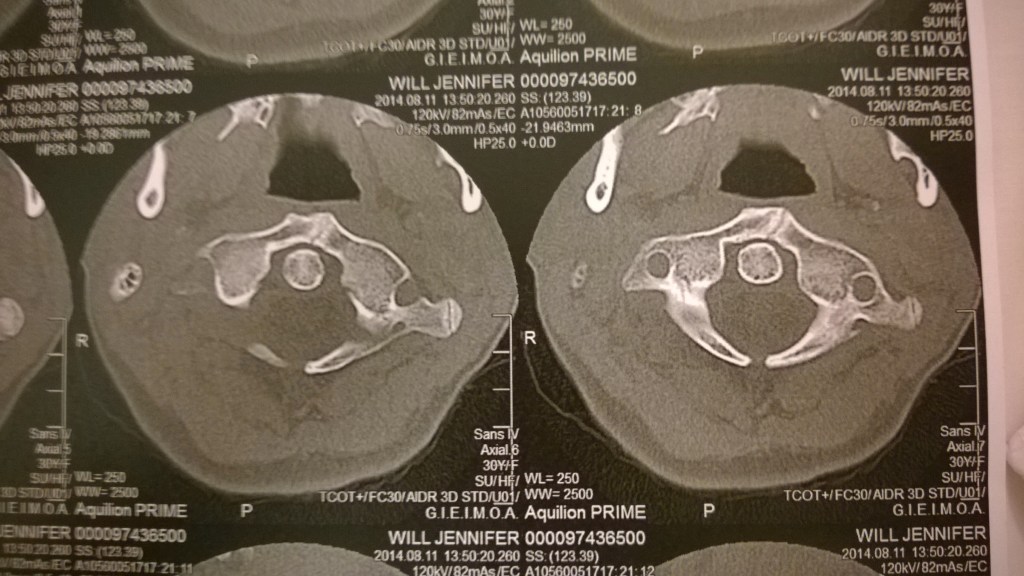

Intressant i ämnet kan vara att mellan kraniet C0 och Atlaskotan C1 och Axis C2 finns inga diskar, utan dessa börjar mellan C2 och C3 och ner genom hela ryggkotpelaren. Så oftast när man besöker sjukvården och får en röntgen (slätröntgen, CT eller MR) så tittar nästan alla bara på C3 och neråt då de vill se hur diskarna har det. Mycket få eller nästan ingen tittar på ligamenten eller ens på C1/C2 förhållandet. Detta är intressant tycker jag!

(Källa och bild: http://www.thepainrelieffoundation.com/craniocervical-instability )